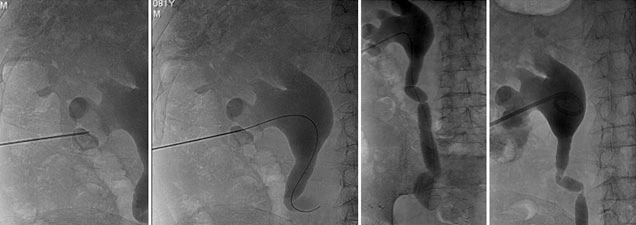

Nefrostomia

La nefrostomia è una procedura in cui viene posizionato un drenaggio percutaneo attraverso la pelle per drenare l’urina direttamente dal rene verso l’esterno. Questa procedura viene eseguita sotto guida radiologica, in cui il radiologo interventista punta il calice renale e inserisce il drenaggio. È spesso necessaria in caso di danni traumatici o iatrogeni delle vie urinarie, oppure per “mettere a riposo” la via escretrice in caso di ostruzioni gravi.

Posizionamento di Stent Nefro-Vescicale

In alcuni casi, viene posizionato uno stent nefro-vescicale quando il drenaggio esterno non è più necessario o desiderato dal paziente. Questo stent può essere posizionato anche in urgenza, ad esempio in presenza di infezioni gravi, insufficienza renale acuta o in pazienti con un solo rene. La sostituzione periodica degli stent può essere eseguita endoscopicamente dall’urologo o sotto guida radiologica dal radiologo interventista, con una procedura rapida e a basso rischio in regime di day surgery.